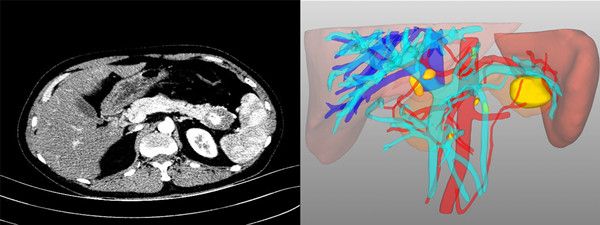

患者1,男,40岁,诊断“原发性肝癌(术后复发)”。术前评估:全身评估及营养评估未见异常;肝功能Child-Pugh-Turcotte分级A级,ICGR15 5.7%;考虑患者系既往解剖性肝段切除后肿瘤复发,故选择解剖性右半肝切除。病灶及可切除性评估:肿瘤位于肝右后叶,毗邻右肝静脉;门静脉无变异(A型),肝动脉无变异,肝静脉无变异;肝内胆管无扩张;患者总肝体积1435.09ml,标准肝体积1314.17mL,右半肝体积523.04mL,左半肝体积占标准肝体积的69.4%(标化余肝率,Rsr),按照《精准肝切除术专家共识(2017版)》要求,患者标化必须余肝率(Rse)为40%

患者2,男,44岁,诊断“原发性肝癌”。术前评估:全身评估及营养评估未见异常;肝功能Child-Pugh-Turcotte分级A级,ICGR15 0.6%;病灶及可切除性评估:肿瘤位于肝脏V-VIII段,约8*7.5*7.5cm大小,侵犯肝右静脉中远端及相应肝段Glisson系统;门静脉无变异(A型),右肝动脉发自肠系膜上动脉,裂静脉与肝中静脉根部共干;肝内胆管无扩张;拟行解剖性右半肝切除术,患者总肝体积1877.27ml,标准肝体积1191.08mL,右半肝体积1126.23mL,左半肝体积为751.04,Rsr为63.1%,结合当前患者肝功能及ICGR15水平,Rse为40% 患者3,男,36岁,诉“发现胰体尾占位1周”,术前诊断“胰体尾实性假乳头状瘤”。患者因颈椎病,在骨科住院查出胰腺占位性病变,转入我科治疗,术前评估:全身评估及营养评估未见异常;肝肾功正常:肿瘤位于胰尾部近脾门处,经三维重建后,可见脾动脉及脾静脉分两支型,紧紧包绕肿块,决定腹腔镜下行胰体尾联合脾脏切除。术中探查见上脾门区致密粘连,给手术来带了一定的困难和挑战。凭借术中三维精准导航和精细的手术解剖,胰体尾及脾脏被顺利切除。手术历时2.0h,术中出血约50mL,目前患者恢复良好,拟于近日出院。 术后在谈及专业划分后一周的肝胆胰外科工作时,陆宏伟教授表示,肝胆胰外科手术操作犹如荒野探险,术前永远无法完全把握未知的前方有哪些解剖变异和挑战等待着你,因此只能通过术前精准的治疗规划、术中结合影像学进行精细的外科操作和术后精心的个体化管理,使患者最大程度的获益。 陆宏伟教授师从于我国著名肝胆胰外科专家董家鸿院士,对于肝胆胰良恶性肿瘤和胆管扩张症的精准诊疗及肝脏移植术具有丰富经验。目前陆宏伟教授团队已与北京清华长庚医院董家鸿院士团队、中国人民解放军总医院段伟东教授团队建立长期临床及科研合作关系,这将进一步提升团队的肝胆胰疾病诊断和外科治疗水平。